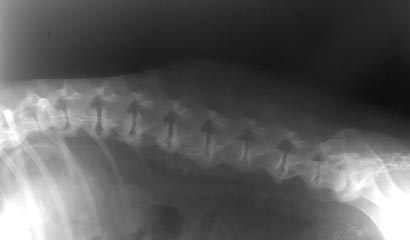

È una malattia degenerativa a carico dei dischi intervertebrali, localizzata in particolare a livello delle vertebre lombosacrali, che porta alla formazione di osteofiti (proliferazioni ossee) con fusione delle vertebre e diminuzione d’elasticità della colonna vertebrale. A ciò consegue una pseudoartrosi dovuta alla contiguità delle formazioni di osteofiti nei due corpi vertebrali adiacenti e della conseguente infiammazione dei tessuti circostanti (osteomielite artrosica). In genere la malattia interessa i soggetti adulti di razza medio grande, in particolare i molossoidi e i Boxer sottoposti a lavoro e/o attività sportive. La diagnosi viene confermata mediante una radiografia latero-laterale della colonna vertebrale, in prossimità della regione lombo sacrale, includendo nell’immagine anche le ultime tre vertebre toraciche, possibile sede di localizzazione della patologia.

La malattia può avere un decorso asintomatico, o altresì, presentare dei sintomi che variano in funzione della progressione della patologia. L’animale ha riluttanza a muoversi, l’andatura è incerta e rigida, in particolare sul posteriore, il cane tende a incespicare anche nei più piccoli ostacoli. Nei casi più gravi si avrà un notevole irrigidimento del rachide e conseguentemente di tutti e quattro gli arti fino alla totale paresi. Questi segni clinici sono dovuti ad un’azione infiammatoria a carico dei tessuti vicini alla zona colpita, con conseguente compressione dei nervi spinali dovuta alla presenza dei suddetti osteofiti. Tali vegetazioni ossee si possono rilevare sia nella porzione toracica, che in quella lombare e lombosacrale della colonna vertebrale. L’immagine radiologica disegna questi osteofiti come prominenze radiopache (cioè della stessa immagine dell’osso) di differenti dimensioni, che nel tempo tendono a ingrandirsi assumendo una figura caratteristica detta a “becco di pappagallo”. Nei casi gravi o in quelli molto avanzati questi ponti ossei tendono a unirsi tra loro, anche se il più delle volte vi è una semplice “interdigitazione”, cioè una sovrapposizione degli osteofiti stessi soprattutto nei tratti della colonna vertebrale che possiede una maggior mobilità.